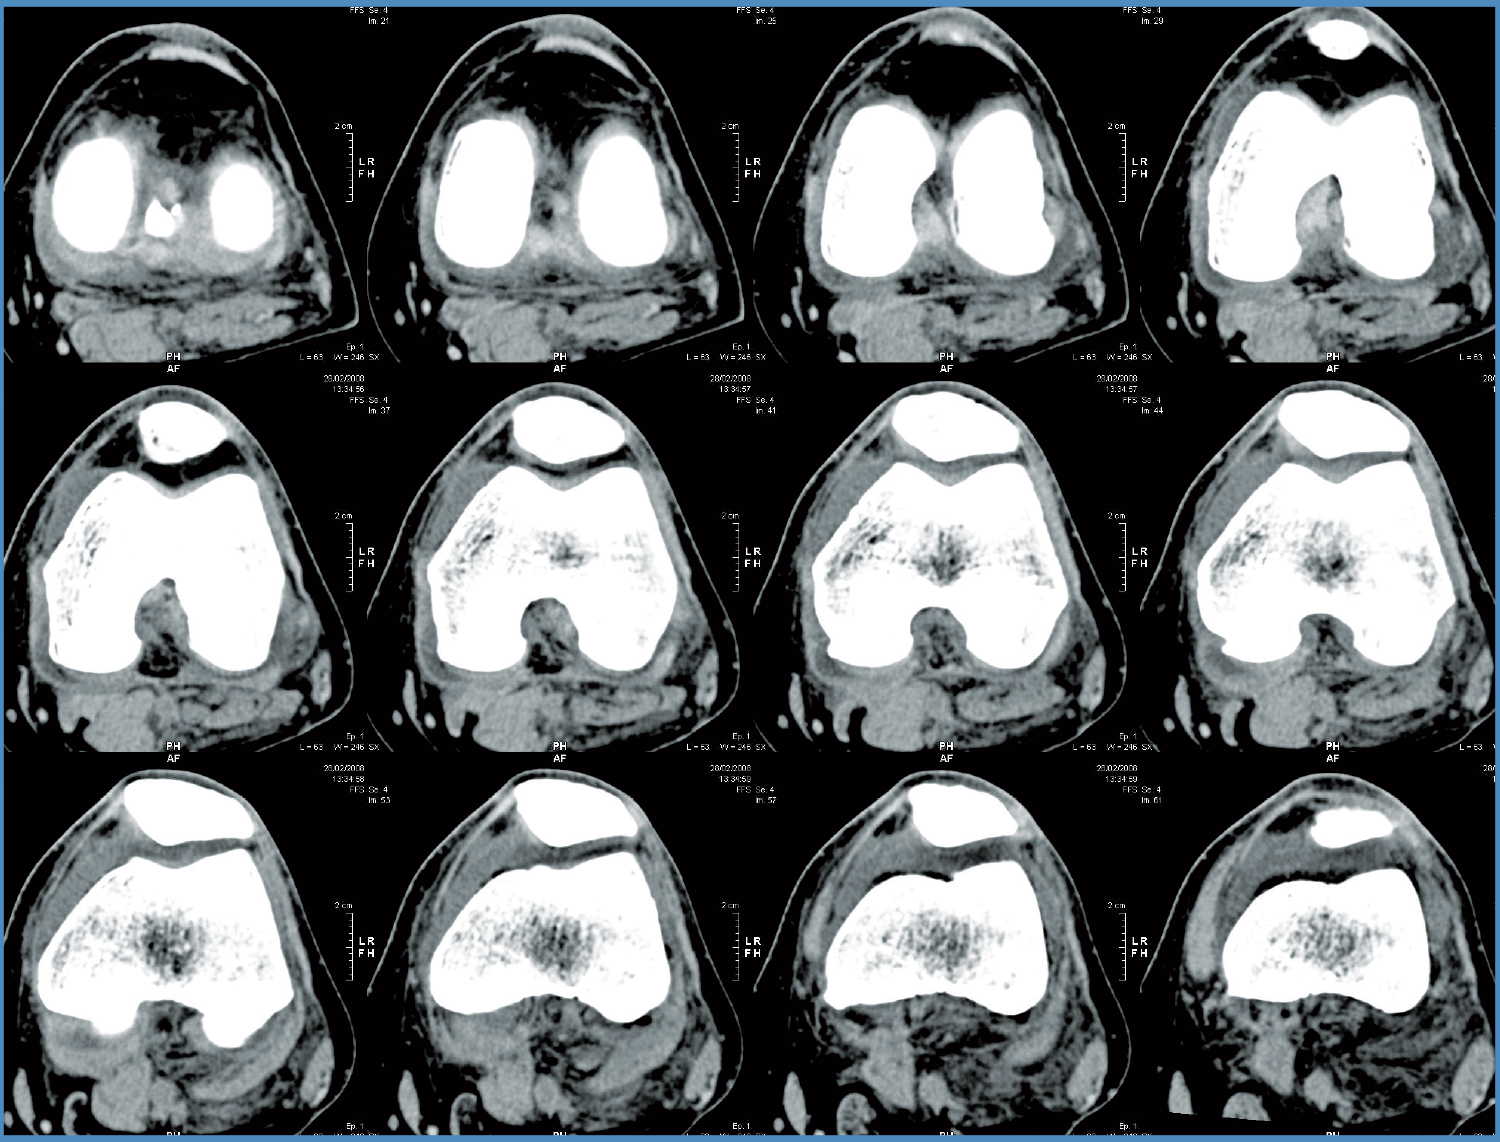

Mako Robotic-Arm Assisted Technology provides you with a personalized surgical plan based on your unique anatomy. First, a CT scan of the diseased knee joint is taken. This CT scan is uploaded into the Mako System software, where a 3D model of your knee is created. This 3D model is used to pre-plan and assist your surgeon in performing your partial knee replacement.

Step 1. Knee CT Scan